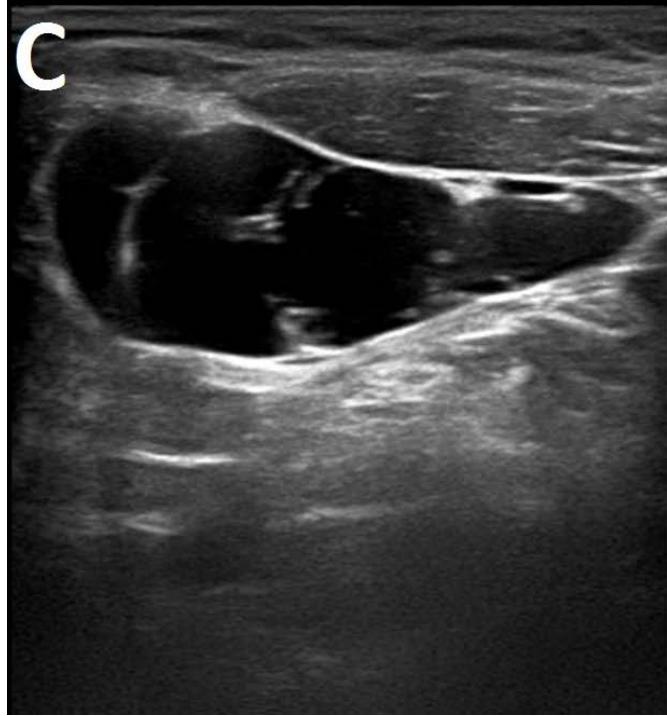

Figure/Patient 1

A 7 year-old girl presenting with a tumefaction at the level of the right latero-cervical region. US scans show a $43 \times 14$ mm subcutaneous fluid formation with septa extending from the root of the neck to the submandibular region (A-B). Doppler-mode demonstrates lack of blood flow within the lesion or the septa (C-D). Diagnosis of cystic lymphangioma is done.